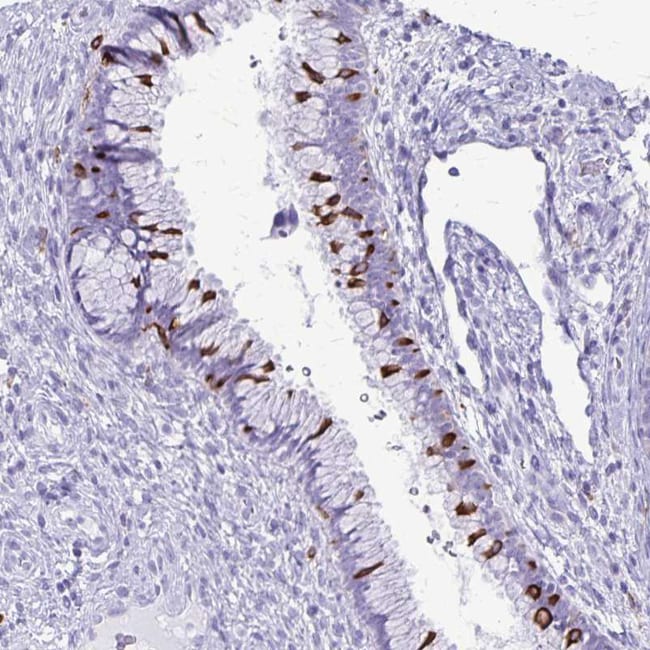

Invitrogen™ RTN1 Polyclonal Antibody

Immunogen sequence: SITPPSSGTE PSAAESQGKG SISEDELITA IKEAKGLSYE TAENPRPVGQ LADRPEVKAR SGPPTIPSPL DHEASSAESG DSEIELVS Highest antigen sequence indentity to the following orthologs: Rat - 85%, Mouse - 86%.

| Applications | Immunohistochemistry (Paraffin), Immunocytochemistry, Immunohistochemistry (Paraffin) |